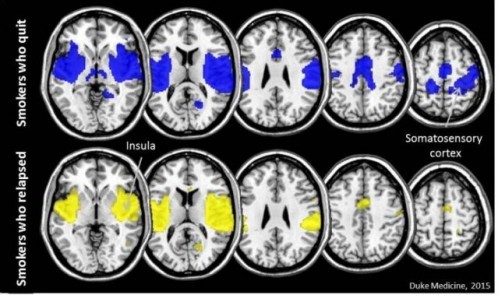

اما ۴۴ نفر از آنها موفق شدند که سیگار کشیدن را بطور موفقیت آمیزی کنار بگذارند؛ نتایج مطالعه محققان از روی ام.آر.آی این افراد نشان داد که در تمامی آنها دو قسمت از مغزشان به نام اینسولا و قشر somatosensory ارتباط زیادی بهم داشت.

این مطالعه نشان داد که ارتباط میان این دو قسمت از مغز برای ترک سیگار مهم است.

از سوی دیگر قشر حسی-پیکری (somatosensory) مغز ، کنترل کارکردهای حسی و حرکتی را بر عهده دارد. این مطالعه نشان داد که ارتباط میان دو بخش اینسولا و قشر somatosensory در افرادی که موفق شدند سیگار را ترک کنند، بیشتر بود.